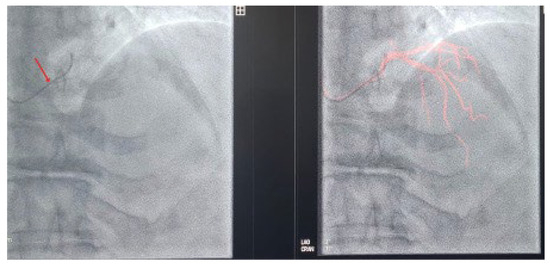

Expanding Applications of Three-Dimensional Cardiac Mapping Systems: A Review

by Rabeia Javid, Stephen O. Otieno, Stephen B. Wheatcroft, Sacchin Arockiam and Muzahir H. Tayebjee

Percutaneous coronary intervention (PCI) is a widely performed revascularisation procedure for coronary artery disease. Although effective, its reliance on fluoroscopy and iodinated contrast exposes patients and operators to risks of radiation and nephrotoxicity. As PCI techniques have become more complex, interest has grown [...] Read more.

Percutaneous coronary intervention (PCI) is a widely performed revascularisation procedure for coronary artery disease. Although effective, its reliance on fluoroscopy and iodinated contrast exposes patients and operators to risks of radiation and nephrotoxicity. As PCI techniques have become more complex, interest has grown in imaging methods that reduce dependence on fluoroscopy and contrast. Electro-anatomical mapping systems (EAMS), developed for catheter navigation in electrophysiology, enable real-time three-dimensional visualisation without the need for fluoroscopy or contrast. By adapting coronary guidewires as electrodes, EAMS can reconstruct vessel anatomy and track interventional tools in real time. EAMS have demonstrated feasibility and safety in device implantation, and early studies suggest their applicability to PCI, where they may mitigate radiation and contrast exposure by providing an alternative method for guidewire and stent visualisation. This review provides a narrative overview of current evidence, outlining the technical principles, applications in device implantation, and the emerging role of EAMS in coronary intervention. Full article